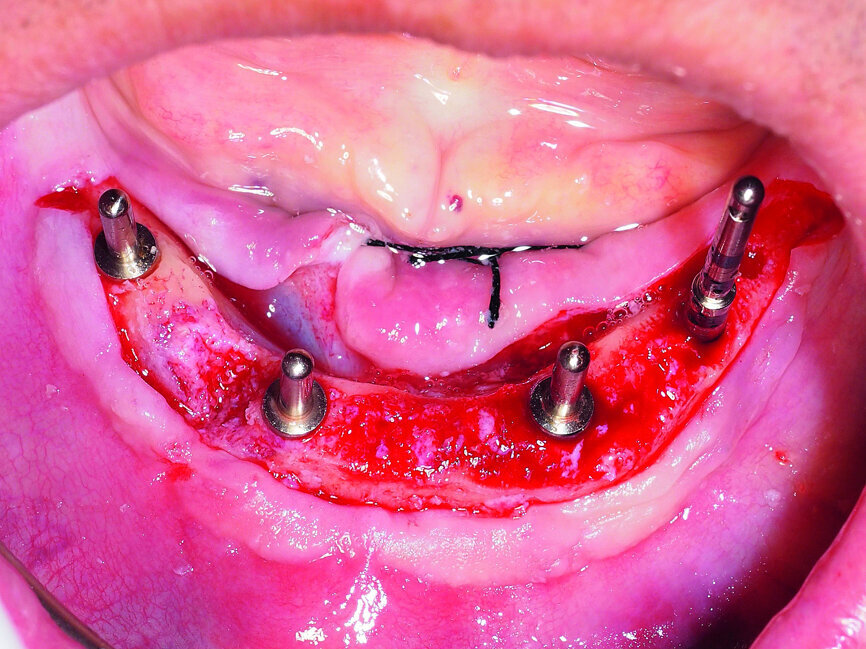

Fig. 2: Placement of four GC Aadva implants in the interforaminal region.

Regarding the occlusion-related factors, it is important to note that the implant placement should be precise and prosthodontically driven, bearing in mind the biomechanics of the final restoration. This means minimising the adverse leverage loads by centring implants in the mesiodistal plane, placing them perpendicular to the occlusal plane, choosing key implant positions and avoiding cantilevers (Figs. 1 & 2).[24] Moreover, the occlusion must be well-balanced with particular regard to patients with high masticatory forces and parafunctional habits.

A demonstration of this technique is shown in Figures 13 to 20. This case presents an elderly woman who had lost her teeth in the lateral mandible decades ago. Being a healthy non-smoker with good oral hygiene, no history of periodontal disease and low masticatory forces, she was an adequate candidate for bone grafting together with implant placement. The future restorative margins allowed the usage of ridge splitting (Figs. 13 & 14). Therefore, we opted for a ridge split with vertical releases carried out utilising a partial-thickness flap. The periosteum was left attached in order not to impede the perfusion of the buccal plate (Fig. 15). After ridge splitting, the buccal and lingual plates were separated with the use of bone spreaders (Split-Control Plus, Meisinger) to allow the placement of two GC Aadva Standard implants, one of 3.3 mm in diameter and 8.0 mm in length and the other measuring 4.0 mm in diameter and 8.0 mm in length (Figs. 16–18).